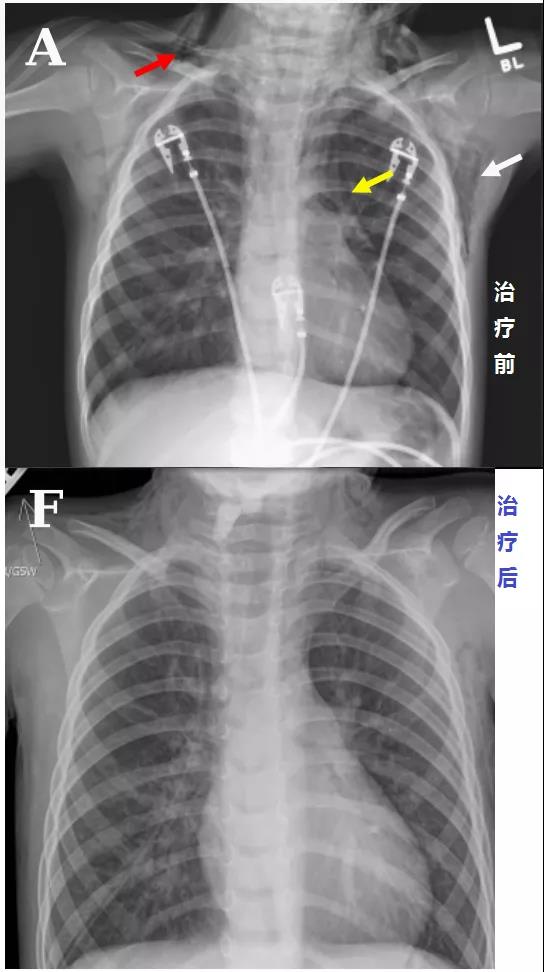

頭顱、胸部CT提示廣泛皮下氣腫、縱隔氣腫、心包積氣、甚至眼眶周圍都積氣,眼球突出!頸部無感染征象,腸管無破裂征象,看來氣體還是來自肺部。但是,肺部無感染、無肺大泡、無劇烈咳嗽,只有間質性肺氣腫。縱隔氣腫、皮下氣腫的治療,核心是根除病因,切開引流效果不像氣胸那么理想,而且縱隔切開引流還存在手術風險。找不到病因,如何是好?考慮患者是過敏體質,有皮疹,繼續呼吸機輔助呼吸,先治療過敏,肌肉注射腎上腺素、靜脈注射類固醇激素和抗組胺藥、吸入支氣管擴張劑等。經上述治療,臨床表現和影像學方面都有迅速的改善。隨后拔出氣管導管,口服類固醇激素出院,門診隨訪。

皮下氣腫、縱隔氣腫突然莫名其妙的就消失了!呼吸機治療可是會加重縱隔氣腫啊!這個皮下氣腫、縱隔氣腫,真的是來去一陣風啊,堪稱神出鬼沒!過敏反應一般表現為皮疹、皮膚瘙癢,嚴重的表現為休克,甚至引起喉頭水腫、氣管和支氣管痙攣及肺水腫導致呼吸困難,其他表現有昏迷、剝脫性皮炎型藥疹等多器官損害。沒聽說過敏反應還會導致廣泛皮下氣腫、縱隔氣腫、心包積氣,甚至眼眶周圍都積氣,眼球突出啊!過敏反應可引起急性支氣管痙攣,進而氣道壓力升高,導致肺泡破裂,空氣進入組織間隙,并沿肺間質內血管鞘進入縱隔,導致縱隔氣腫,只形成間質性肺氣腫,并不會導致我們平時所見的氣胸。這個病例提供了一個罕見的藥物過敏反應方面的臨床表現,對于存在這種特異質的兒童來說,如果不早發現、早治療,隨時可能致命。另外,大家有沒有發現,患者因咽炎口服阿莫西林,才吃了1次,后來過敏,咽炎沒繼續治療,也好了!在患者的咽炎治療過程中,阿莫西林除了引起危及生命的過敏反應,并未扮演其他有任何價值的角色!Jacob A. Kaslow, MD,Elizabeth J. Snyder, MD,Brian C, et al. Massive Facial, Neck, and Chest Air Leaks Following Amoxicillin-Related Anaphylaxis in a Young Child. AJRCCM Articles in Press. Published on 10-January-2020 as 10.1164/rccm.201908-1596IM.